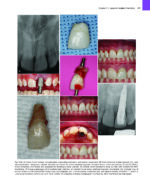

Successfully expand the use of lasers in your dental practice!With vibrant, detailed clinical images and easy-to-follow writing, Principles and Practice of Laser Dentistry, 3rd Edition walks you through the most common uses of lasers in areas such as periodontal surgery, dental implants, prosthetic and cosmetic reconstruction and describes how lasers work, how they interact with tissues, and how this knowledge may be applied to dental practice with a focus on technology, surgical techniques, and key steps in treatment. Written by laser dentistry pioneer Dr. Robert A. Convissar and a team of leading experts, this edition includes an ebook free with each purchase of a print book, three new chapters, and new case histories and clinical tips. It contains everything you need to know to build your skills in the rapidly growing field of laser dentistry